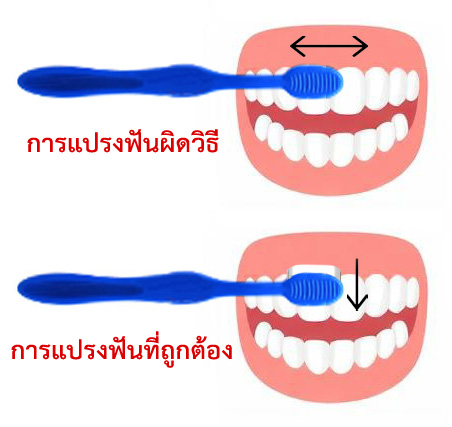

- การแปรงฟันผิดวิธี : แปรงฟันแบบเลื่อยในแนวนอน รวมถึงใช้แปรงสีฟันที่ขนแปรงแข็งเกินไป ต่อเนื่องเป็นระยะเวลานาน

ภาวะเหงือกร่นสามารถเกิดขึ้นจากการแปรงฟันที่ผิดวิธีอย่างต่อเนื่องเป็นระยะเวลานานได้ โดยการแปรงฟันผิดวิธีที่พบได้บ่อย คือ การใช้แปรงสีฟันที่ขนแปรงแข็งเกินไปและการแปรงฟันแบบเฉือนหรือเลื่อยในแนวนอนซึ่งจะทำให้เหงือกเกิดการบาดเจ็บสะสมจนเกิดภาวะเหงือกร่นและฟันสึกในตำแหน่งคอฟันได้

การแปรงฟันอย่างถูกวิธีทำได้โดยการวางขนแปรงทำมุมเฉียง 45 องศากับตัวฟันแล้วปัดขนแปรงลงด้านล่างในฟันบน / ปัดขนแปรงขึ้นด้านบนในฟันล่าง